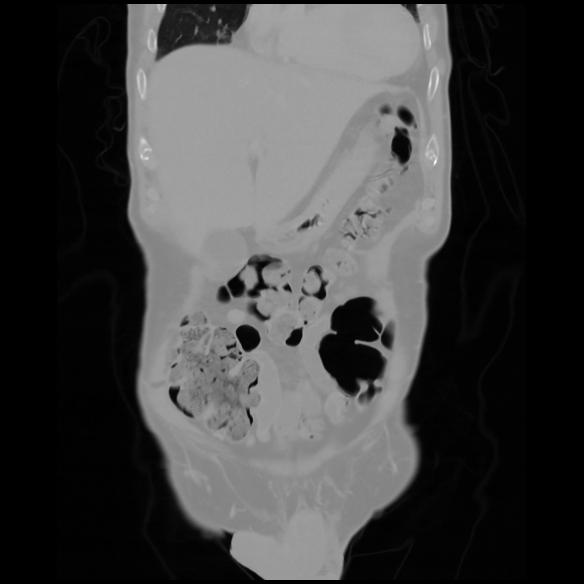

6 CUERPO,CE,Coronal,3.000,CUERPO,Coronal,